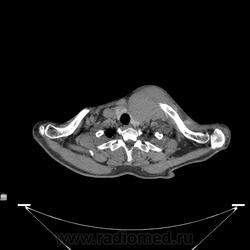

Миелома (плазмоцитома).

Недавний случай. Подтвержден гистологически.  По сцинтиграфии дополнительные очаги гиперфиксации РФП с некоторых ребрах и крестцово-подвздошных сочленениях.